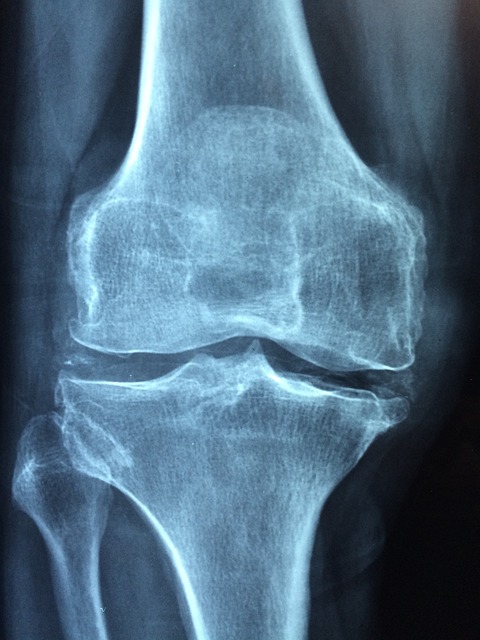

또한 인대가 파열되었거나 찢어진 경우 수술을 생각해 봅니다. 수술은 대게 전방 십자인대에 문제가 발생했을 때 하게 됩니다. 십자인대에 문제가 생기면 무릎을 앞뒤로 움직이는데 어려움을 겪게 됩니다. 비록 젊은 나이에는 하체에 근육이 많은 경우 십자인대가 끊어져도 무릎 통증이 완화되고 나서는 일상생활을 하는데 큰 무리가 없습니다.

하지만 노화에 따라 근육이 감소하다 보면 무릎 관절을 잡아 주던 인대가 끊어졌기 때문에 관절이 이탈되어 변형을 초래할 수 있습니다. 또한 인대는 복원이 되지 않기 때문에 진료 후 인대에 문제가 생겼다면 수술을 받는 걸 추천드립니다. 또한 무릎 반월상 연골이 찢어진 경우 악화되는 것을 방지하기 위해서도 수술을 하는 게 좋습니다.